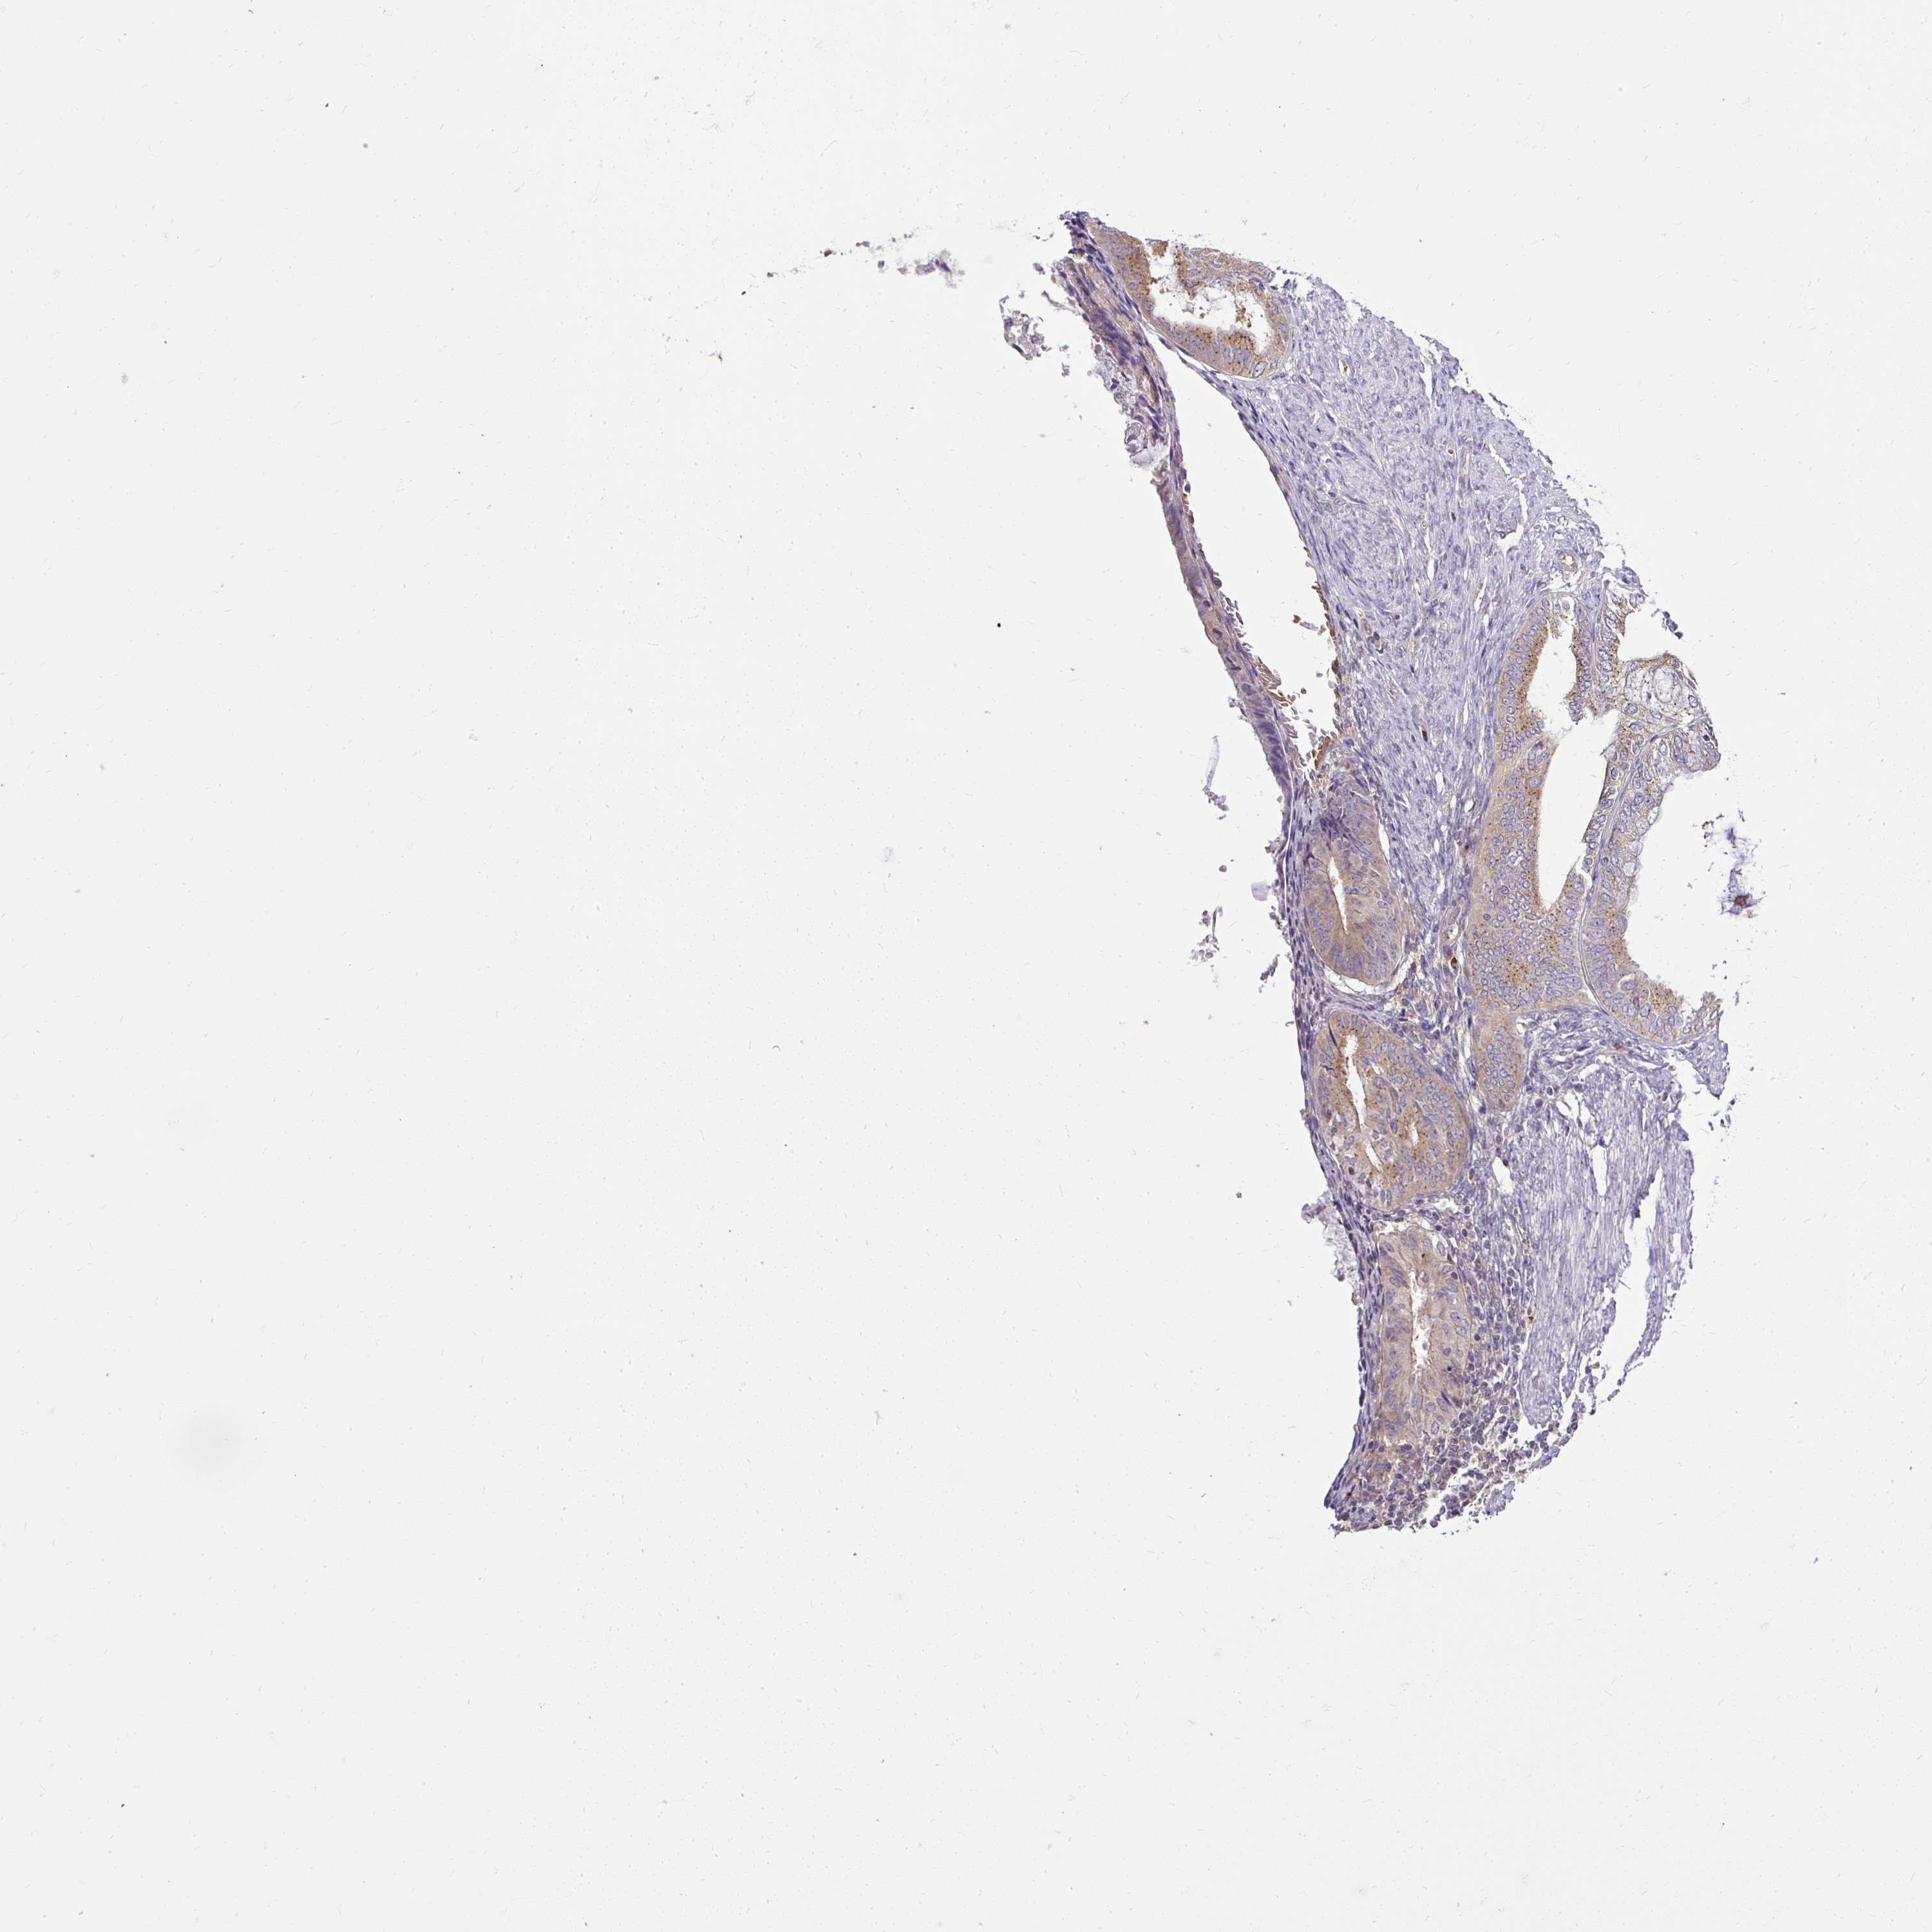

ENDOMETRIAL CANCER - Protein expressioni

A mouse-over function shows sample information and annotation data. Click on an image to view it in a full screen mode. Samples can be filtered based on level of antibody staining by selecting one or several of the following categories: high, medium, low and not detected. The assay and annotation is described here.

Note that samples used for immunohistochemistry by the Human Protein Atlas do not correspond to samples in the TCGA dataset.

Antibody stainingi

Antibody staining in the annotated cell types in the current human tissue is reported as not detected, low, medium, or high, based on conventional immunohistochemistry profiling in selected tissues. This score is based on the combination of the staining intensity and fraction of stained cells.

Each image is clickable and will lead to virtual microscopy that enables deeper exploration of all samples and also displays staining intensity scores, fraction scores and subcellular localization as well as patient and tissue information for each sample.

Antibody HPA029449

Antibody CAB055509

Staining

High

Medium

Low

Not detected

Intensity

Strong

Moderate

Weak

Negative

Quantity

>75%

75%-25%

<25%

None

Location

Nuclear

Cytoplasmic/membranous

Cytoplasmic/membranous,nuclear

Adenocarcinoma, NOS